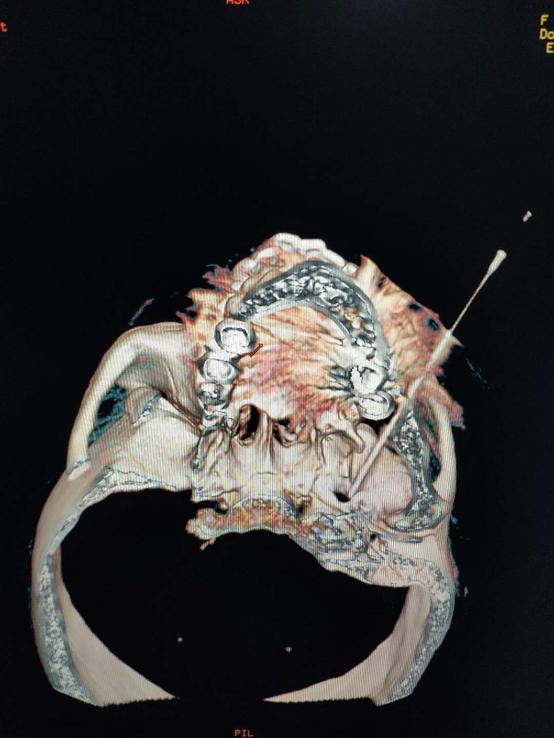

4.CT引导下三叉神经射频消融术